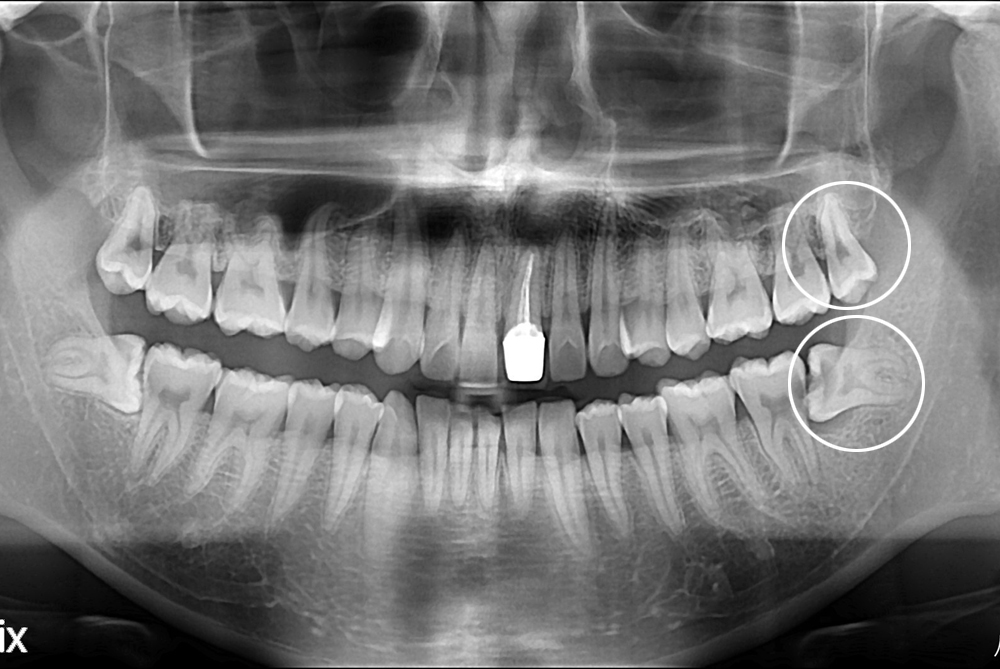

[사랑니] 난발치 사랑니 발치

치료후 : 2017-03-28

세종치과는 구강악안면외과학 박사이신 원장님이 발치하는 치과입니다.